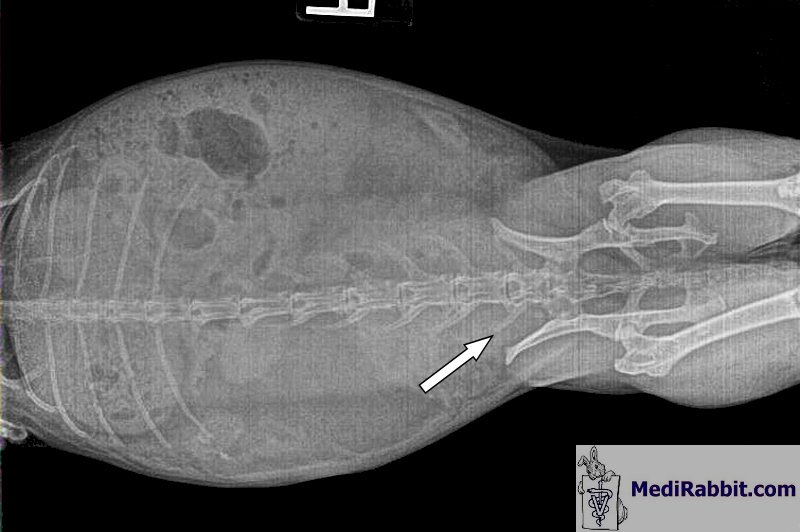

may clear sludge over a longer period of time. Scotchie is a 6 year

old house rabbit. He has been battling bladder sludge for a while, at least 5

years, and needed bladder flushes regularly. These radiographs were taken

before liquid magnesium was administrated and show that his bladder is full

of sludge.

After the last bladder flushing in January (first 2

radiographs), we started giving him 1cc of liquid magnesium daily in his

water. This was recommended by Megan Mather, a rabbit owner who sprinkles

liquid magnesium over fresh vegetables before feeding them to her rabbits Amount: About 1 to 1.5 ml/cc are added to 500 ml of

fresh water (20oz) every morning. At his next

vet checkup in October (10 months later), there was no sludge at all.